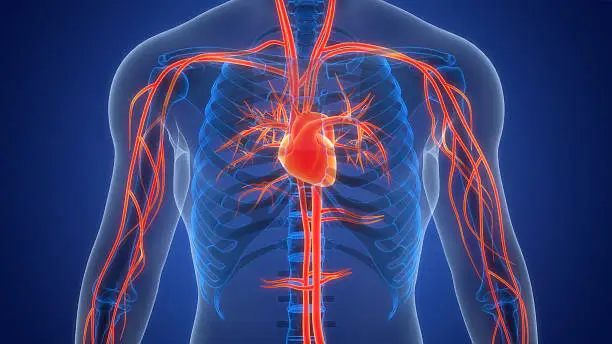

Cardiac Electrophysiologist with expertise in the field of cardiac arrhythmias. Areas of specialisation include pacemaker and heart failure device (CRT / defibrillator) implantations, electrophysiological studies, and radiofrequency ablation.